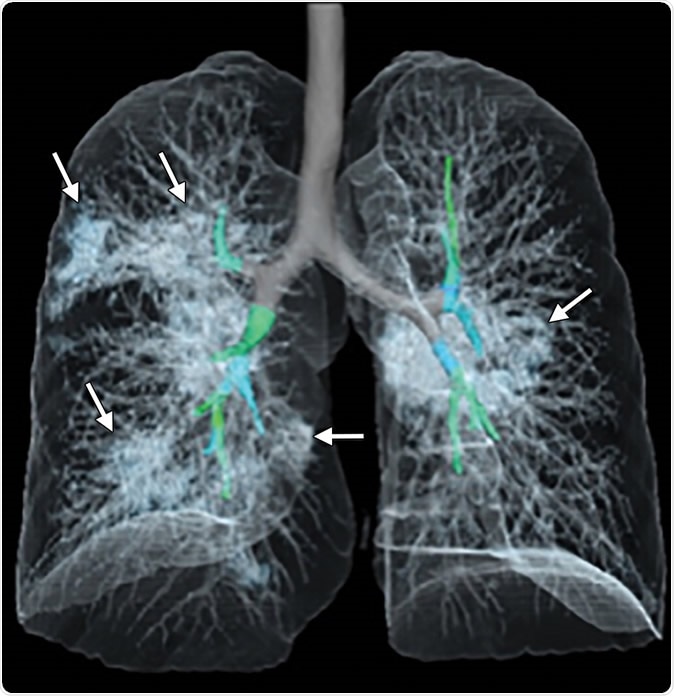

Images in a 41-year-old woman who presented with fever and positive polymerase chain reaction assay for the 2019 novel coronavirus (2019-nCoV). (a) Three representative axial thin-section chest CT images show multifocal ground glass opacities without consolidation. (b) Three-dimensional volume-rendered reconstruction shows the distribution of the ground-glass opacities (arrows). See also three-dimensional Movie (online).